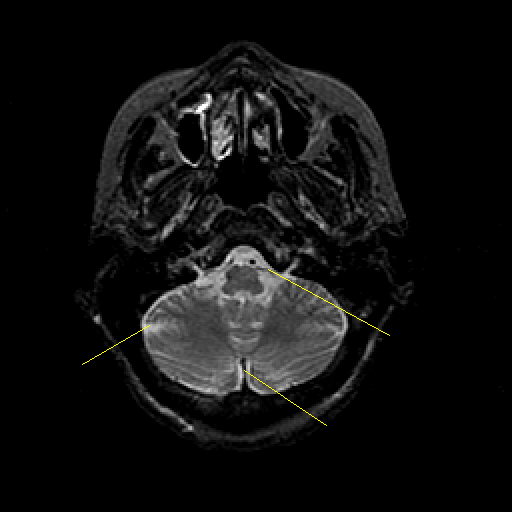

T2-weighted structural MR: Slice 10

Slice 10

Pointers

Labeled